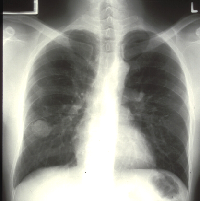

Chest X-ray showing “mass” in right lung due to fluid which resolved without thoracocentesis |